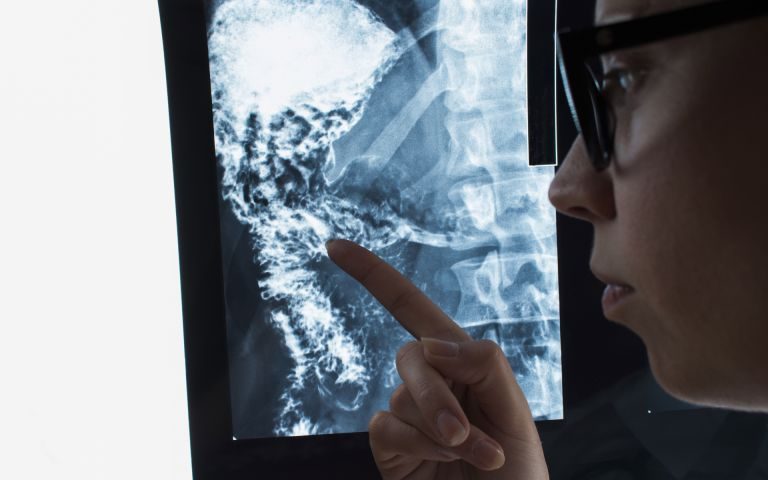

続きを読む大手町のビジネス街に根付く最先端医療と働く人を守る内科の現場